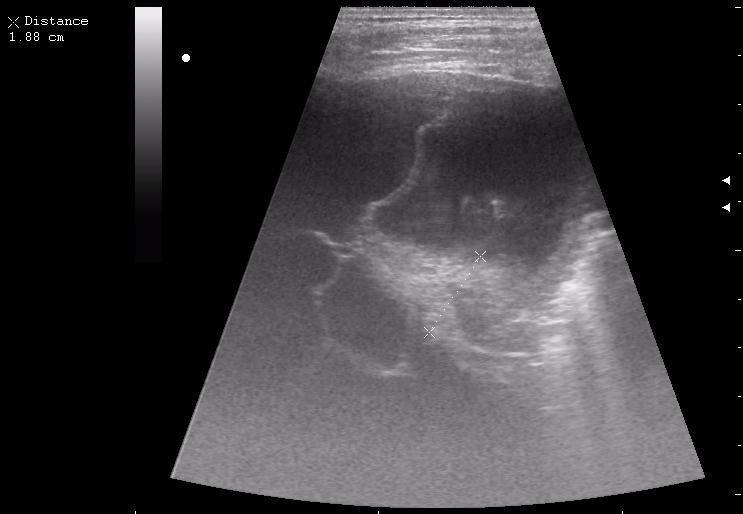

сегментарная пневмония. Экссудативный плеврит.

30790.JPG